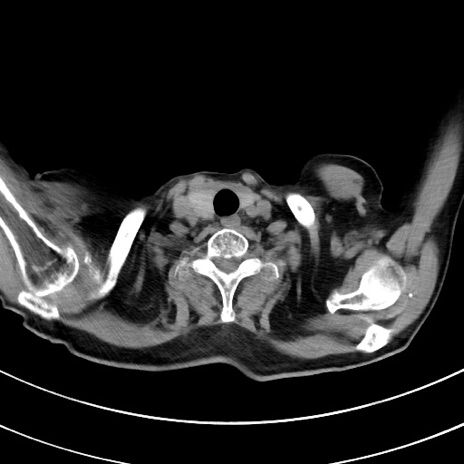

冠状断像